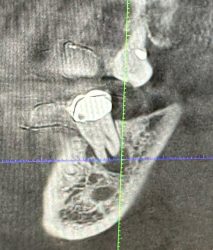

ANDREW started the discussion Infected #8, Pt wants implant in the forum Implant Tx Planning 2 years ago

How would you guys proceed with this case? I am assuming we will need to rebuild the facial wall entirely. Thought about using a titanium mesh membrane tacked down after scrubbing the remaining socket out and placing pt on antibiotics. Question is should we go ahead and graft or wait to heal before grafting and membrane placement?